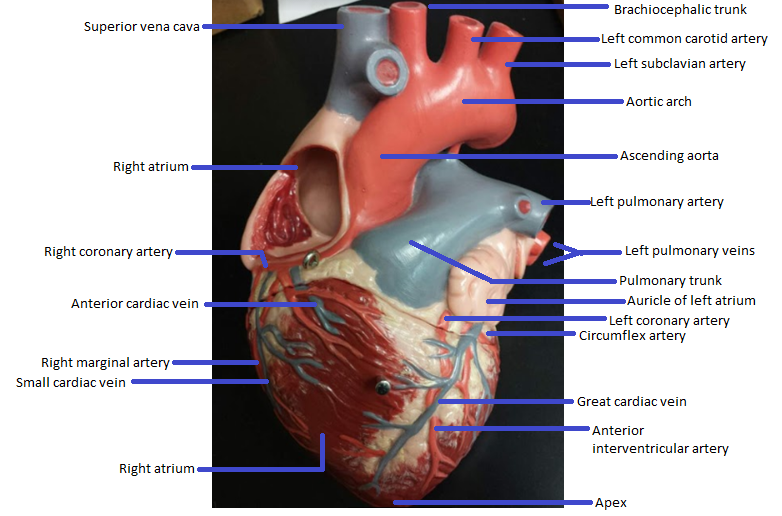

Name the missing parts.

Heart external anterior view